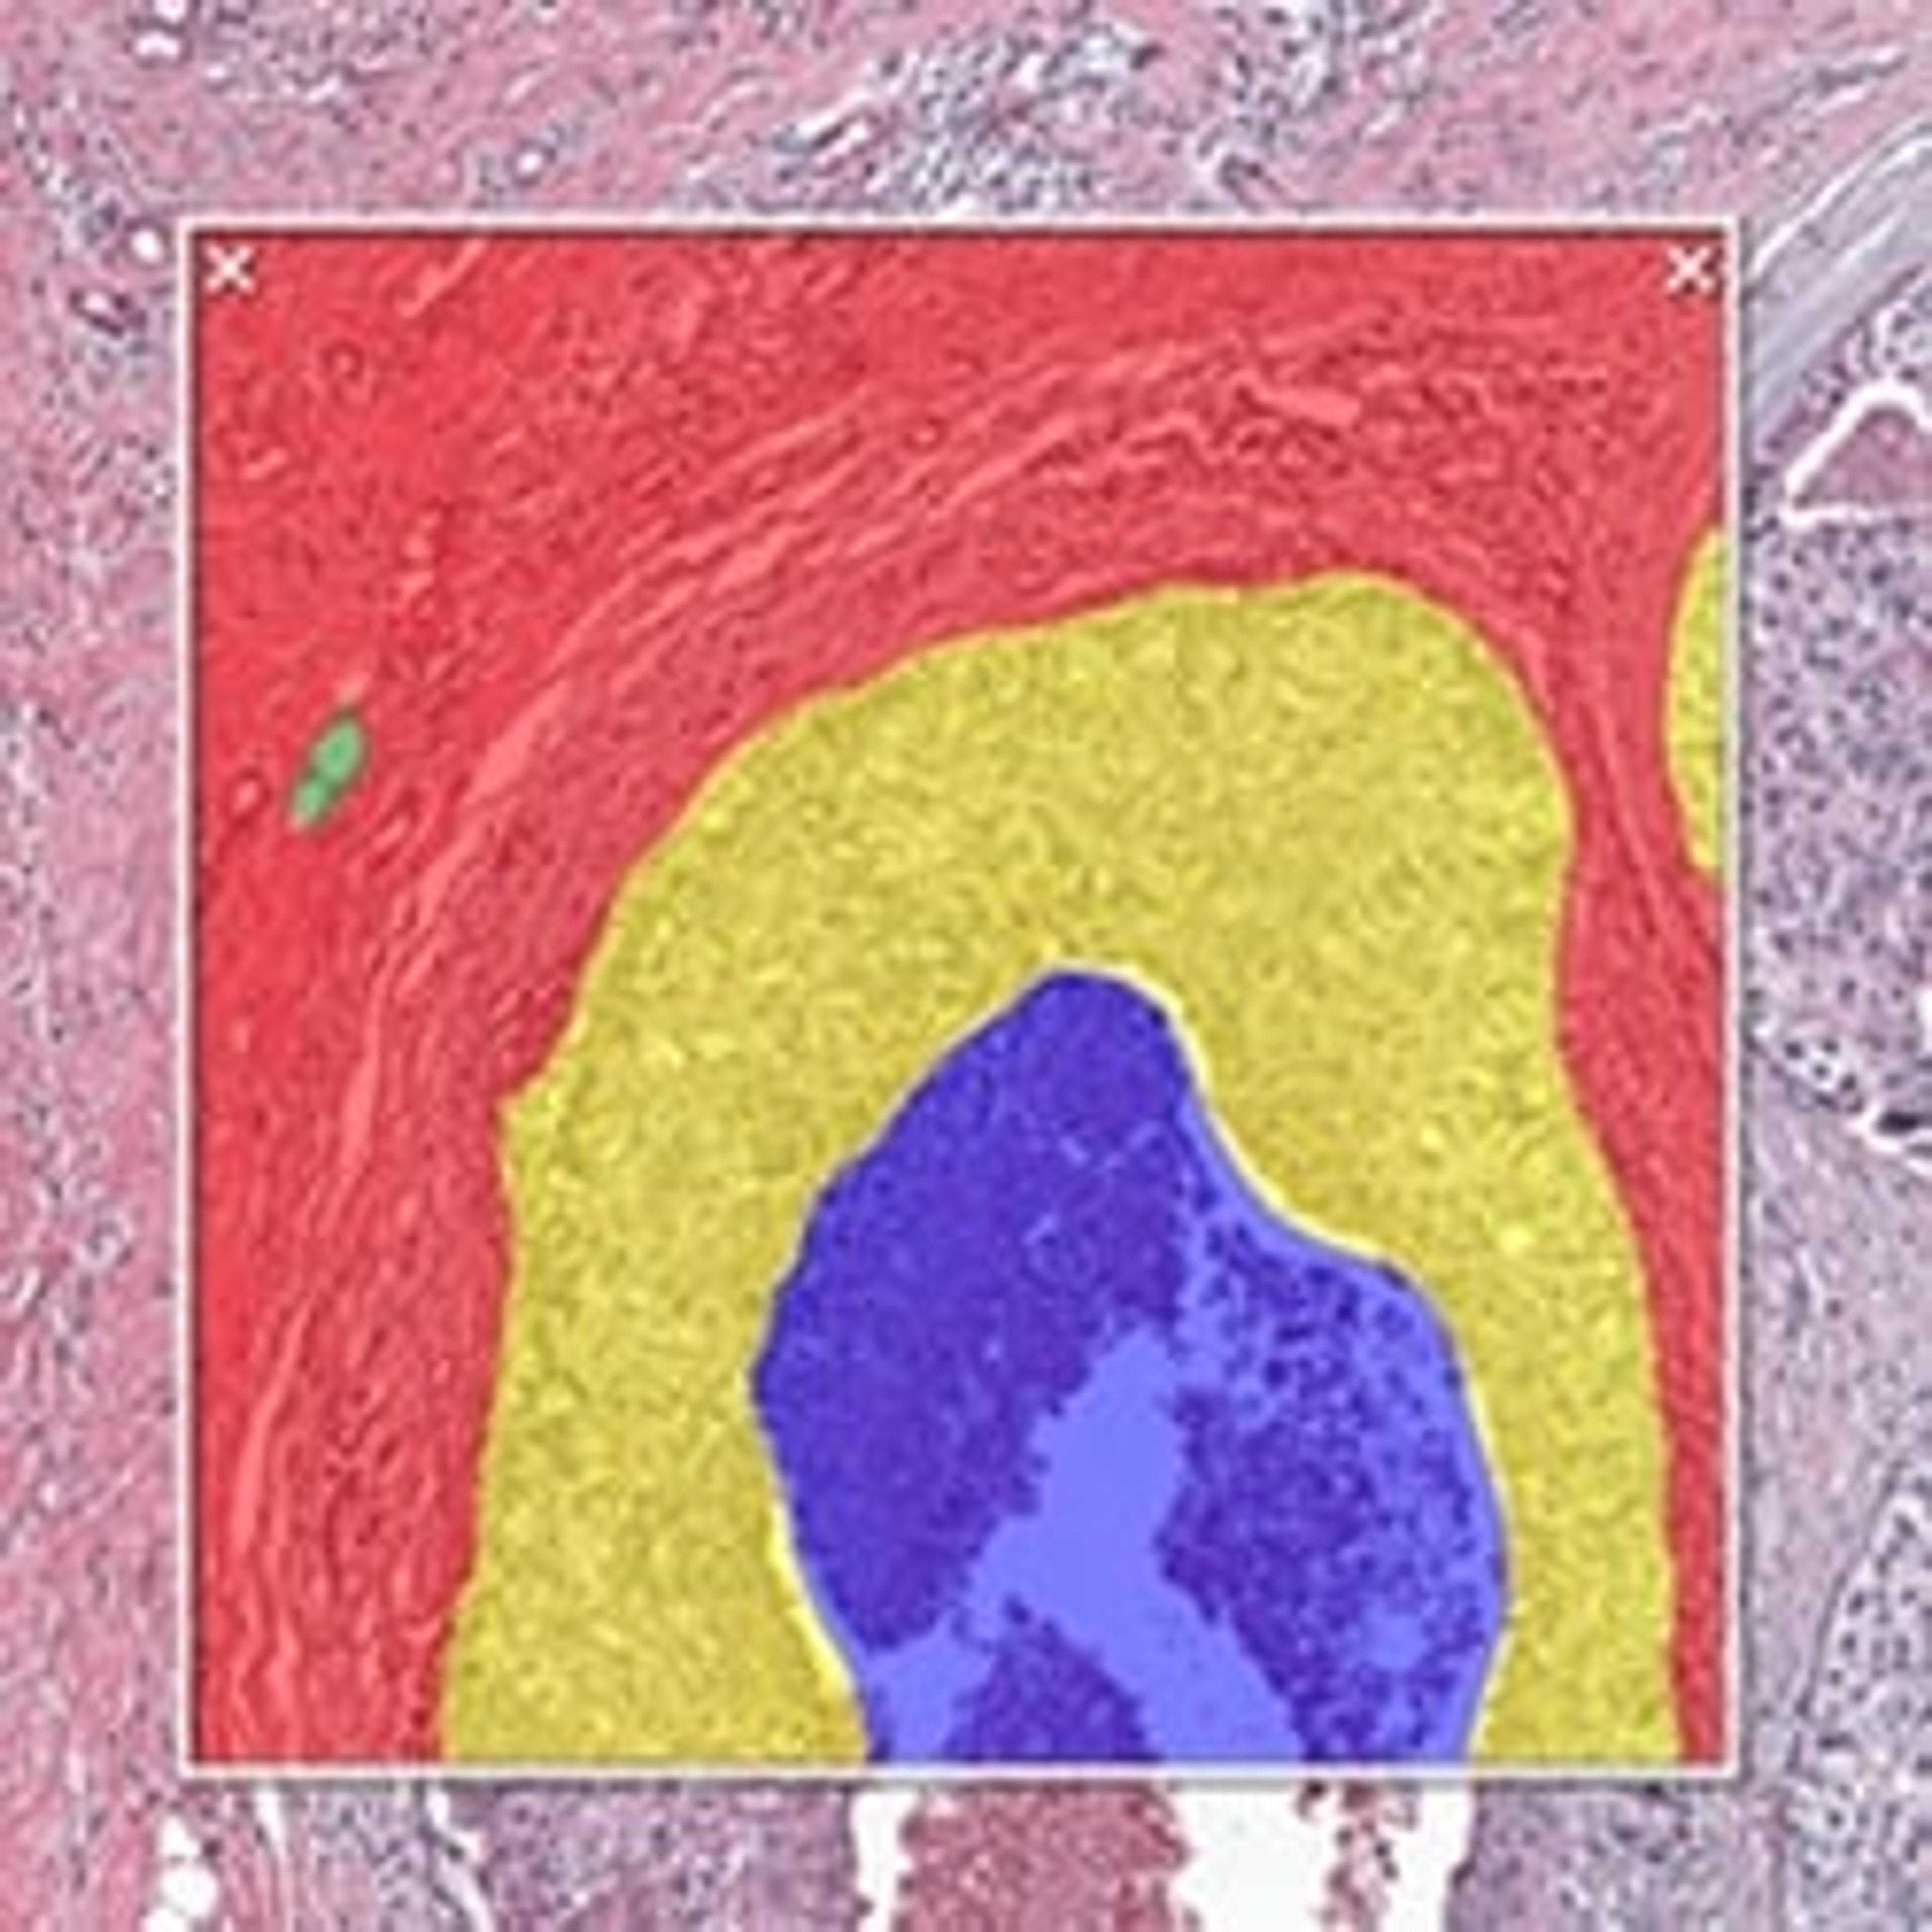

HALO AI is a collection of train-by-example classification and segmentation tools underpinned by advanced deep learning neural network algorithms. HALO AI classifiers can be trained to quantify tissue classes, to segment tissue classes for analysis with other HALO image analysis modules, to find rare events or cells in tissues, and to categorize cell populations into specific phenotypes.

POWERFUL TISSUE SEGMENTATION

HALO AI now includes the option of three powerful neural networks – VGG, DenseNet and MiniNet. VGG, a well-known and more traditional network, was used to build the Indica Labs submission in the CAMELYON17 challenge and was the first neural network integrated with HALO AI. DenseNet is a more modern network capable of creating more robust classifiers at higher resolution compared to VGG. MiniNet, a custom network developed at Indica Labs, is more shallow than VGG or DenseNet, but can produce a solution quickly with limited training data and is therefore useful for testing new AI applications.

EXCEPTIONAL CELL CLASSIFICATION

Segment nuclei with the new Segmentation classifier. Utilize HALO AI’s pretrained networks for H&E, single IHC, or DAPI stained images for an out of the box solution. Or train your own nuclei segmentation network for a specific application (unique tissue or advanced staining protocols). Once nuclei are segmented, take it a step further using the Nuclei Phenotyper classifier to automatically assign cells into user defined phenotypes with a few quick training examples.